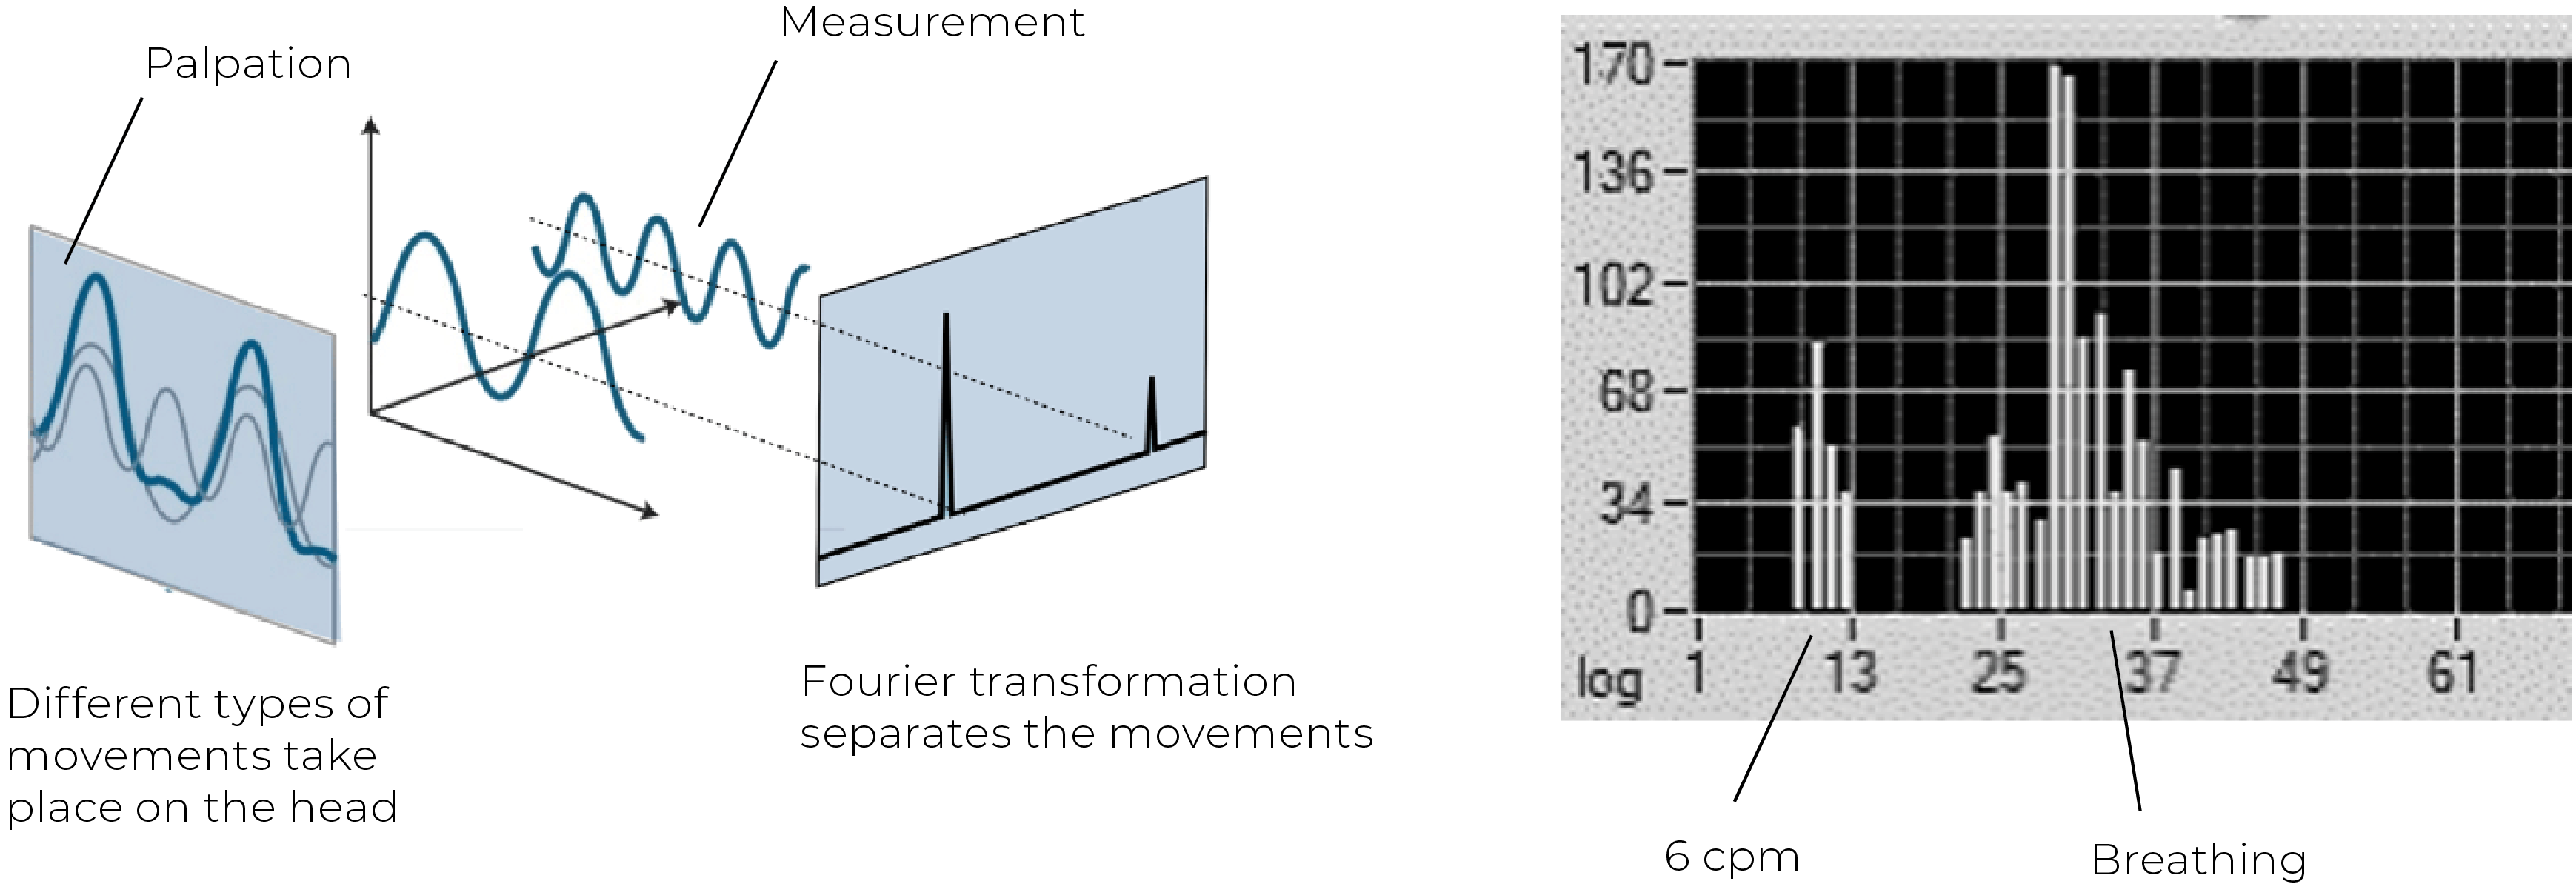

In 2021, Dr. Thomas Rasmussen and Karl Christian Meulengracht published a landmark study, “Direct Measurement of the Rhythmic Motions of the Human Head Identifies a Third Rhythm.”4 Using robotics and software analysis, this was the first direct measurement of cranial rhythms. Micromovements of the head were recorded in 50 healthy adults, alongside respiratory and cardiac rhythms. Their results revealed three consistent rhythms across all participants:

Cardiac rhythm—averaging 57 cpm (range 44–78)

Respiratory rhythm—averaging 14 cpm (range 9–24)

A slower “third rhythm”—averaging 6.16 cpm (range 4.25–7.07)

The third rhythm showed a waveform consistent with palpatory descriptions of the CSR, including flexion, neutral zone, and extension phases. Its amplitude averaged 58 micrometers—large enough to be detected by skilled palpation. This rhythm was distinct from both respiration and cardiac activity, validating long-standing claims by CST practitioners. A key challenge in CSR research has been distinguishing this rhythm from respiratory rhythms. Rasmussen and Meulengracht addressed this by measuring both body and head respiratory rhythms simultaneously.5 Using Fourier transformation analysis, they successfully separated individual rhythms on the head. This clarified why some practitioners palpate rhythms ranging between 4 and 14 cpm—a likely mixing of the CSR and respiratory rhythms. More experienced practitioners, however, consistently identify the slower rhythm near 6 cpm, as documented in a large palpation study of 734 individuals by Nicette Sergueef.6

Today, the normative range of the CSR is converging on 4–8 cpm, supported by both palpatory7 and measurement studies.8 Additional research by Kenneth Nelson and colleagues, using Laser Doppler flowmetry, also identified oscillations in cerebral blood flow near 6 cpm, correlating with palpated rhythms.9